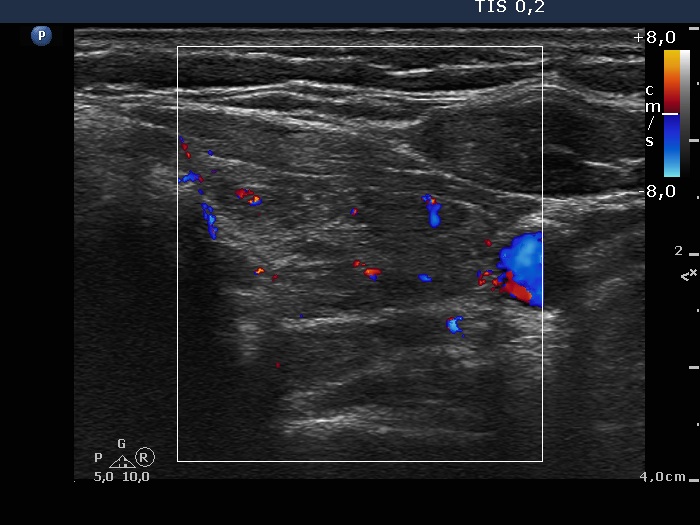

Left lobe, transverse scan, color Doppler mode. The vascularity is average.